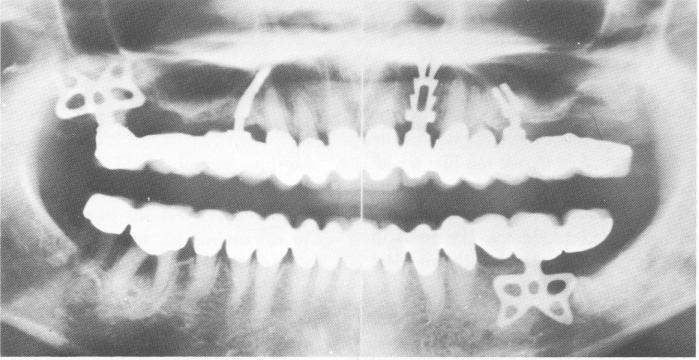

Fig. 11-207. These asymmetrical blades were specially designed to avoid penetrating the sinuses yet give maximum contact with bone.

1 Asymmetrical blades designed to avoid penetrating maxillary sinuses